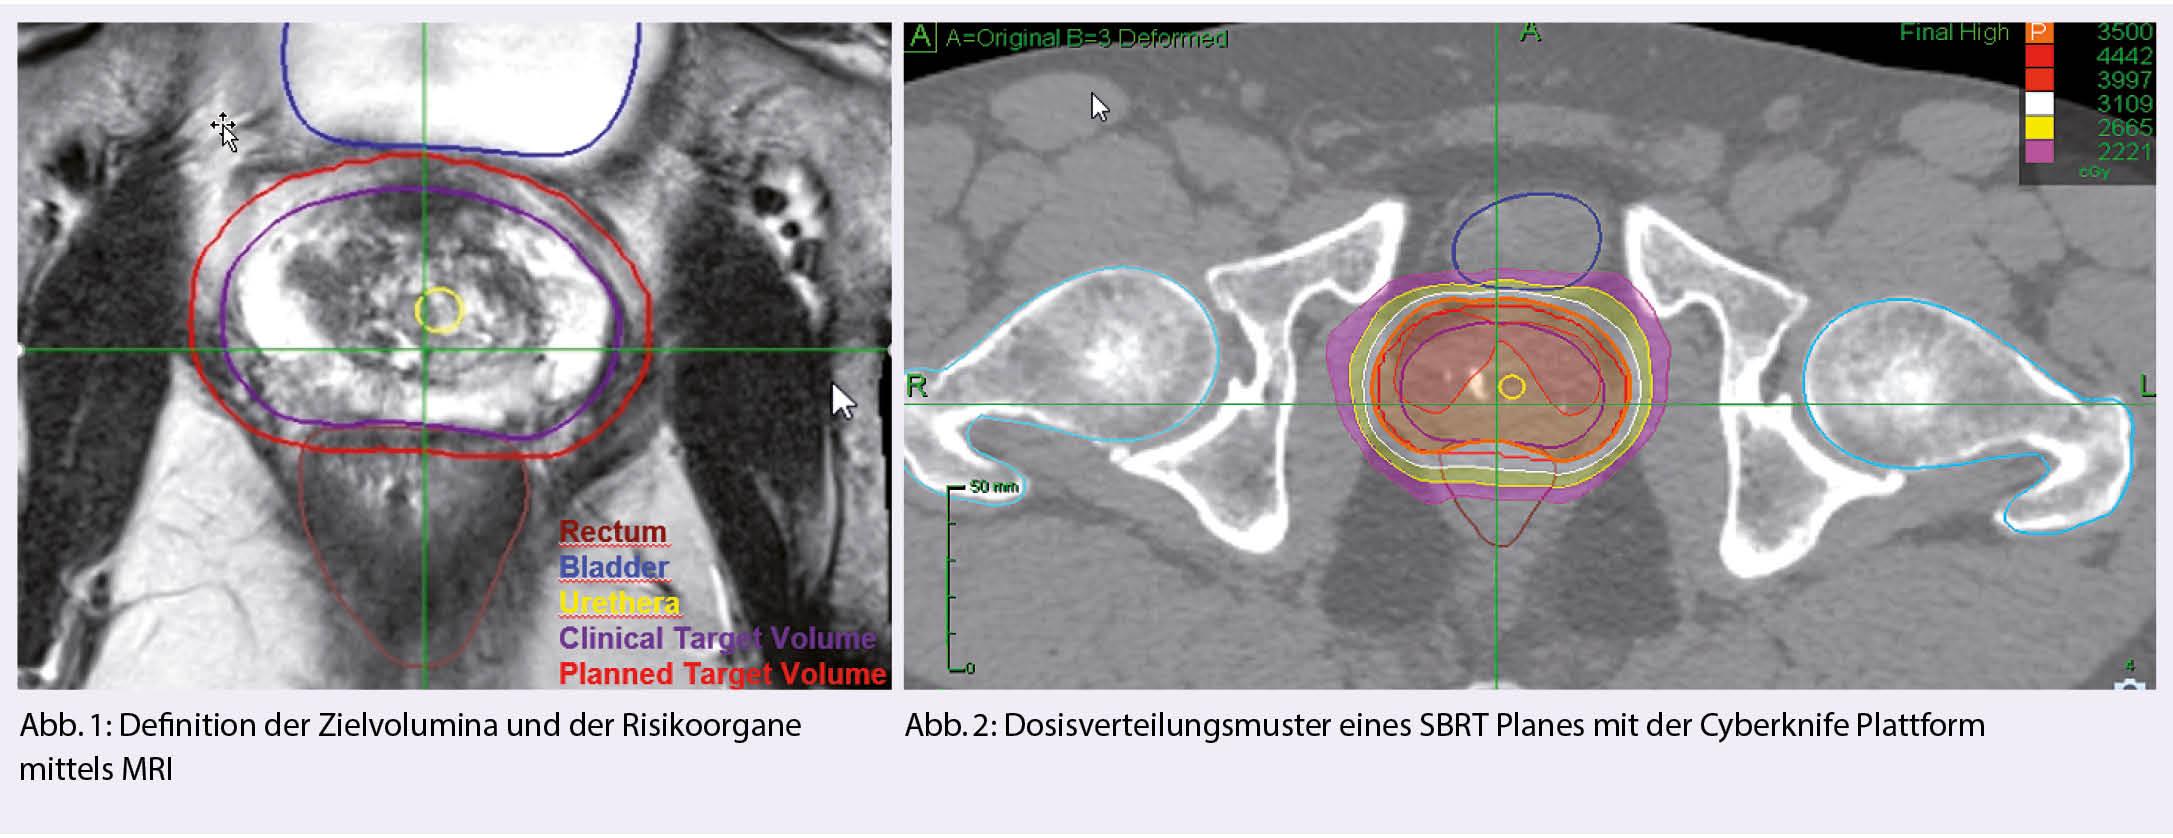

Die Definition des Zielvolumens ist für die Verwendung von SBRT entscheidend. Das Zielvolumen umfasst typischerweise die Prostata, mit oder ohne die proximalen Samenblasen und Bereiche mit extrakapsulärer Ausdehnung. Frühere Studien haben gezeigt, dass bei der Konturierung der Prostata eine signifikante Variation besteht, was die Notwendigkeit einer angemessenen Qualitätssicherung unterstreicht (25, 26). Zunehmend wird die Bildfusion von MRT-Sequenzen in die Praxis umgesetzt. Die Einbeziehung von MRT-Bildern reduziert die Variation zwischen den Beobachtern bei der Zielvolumendefinition im Vergleich zu reinen Computertomographie-Bildern.

In der Mehrheit der bisherigen veröffentlichten Studien wurde das CyberKnife zur Durchführung von SBRT verwendet, in neueren Serien wurde auch von Gantry-basierten Linacs mit ähnlichem Outcome berichtet (27, 28). Die grösste technische Herausforderung bei der Anwendung von SBRT auf die Prostata ist das Management der Beweglichkeit der Prostata während der Bestrahlung. Bildleitsysteme sind der Schlüssel zu einer sicheren Verabreichung von SBRT (Realtime Motion Tracking Systeme).